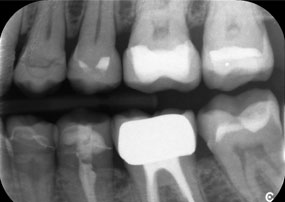

A second case highlighting the clinical capabilities of the Power Edition involved the replacement of a damaged zirconia crown in a 63-year-old patient. The patient presented with a chipped veneer on her 20-year-old zirconia crown on tooth 6. Despite the posterior location, the patient found the defect bothersome and requested a new restoration.

The Power Edition enabled precise sectioning, with the increased torque and enhanced cooling contributing to the controlled removal of the crown without significant material loss. The chucking system and enhanced torque proved to be essential in this process.

A x-ray, showing teeth and a zirconia crown, in front of a black background.

Figure 2: Replacement of a damaged zirconia crown: Precise removal and renewal of a damaged zirconia crown on tooth 6 with minimal material loss.